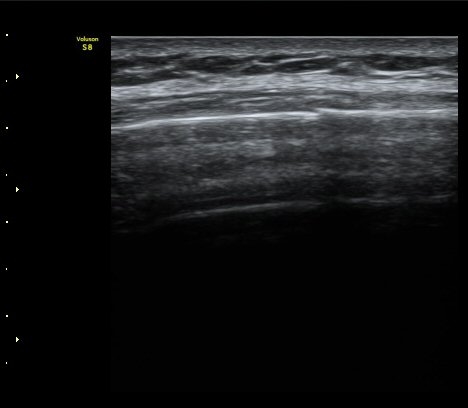

°¥ºñ»À Á¾´Ü¸é°Ë»ç¿¡¼­ °¡°ñ Çü¼ºÀÌ °üÂûµÊ(formation of callus) »çÁø 3

°ñ À¯ÇÕÀÌ È®ÀεÊ.